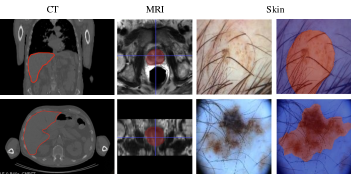

In this section, we evaluate the performance of the proposed method on three commonly used fully convolutional segmentation networks which leverage skip connections: U-Net (both 2D and 3D), V-Net (both 2D and 3D), and the One Hundred Layers Tiramisu network (both 2D and 3D). As U-Net and V-Net were originally designed for biomedical image segmentation, we tested the proposed method on a series of volumetric (3D) and 2D medical imaging datasets (Fig. 3) including (i) a magnetic resonance imaging (MRI) dataset; (ii) a skin lesion dataset; and (iii) a computed tomography (CT) dataset.

Volumetric CT liver segmentation. In this experiment, the goal is to segment the liver from CT images. We used more than 2000 CT scans (to the best of our knowledge this is the largest CT dataset used in the literature so far) of different resolutions collected internally and from The Cancer Imaging Archive (TCIA) QIN-HEADNECK dataset [3, 9, 5], which were resampled to isotropic voxels of size . The QIN-HEADNECK dataset is originally collected from a set of head and neck cancer patients. It has multiple whole body positron emission tomography/computed tomography (PET/CT) scans before and after therapy. However, here we use the CT scans for the purpose of liver segmentation. We picked 61 challenging volumes of whole dataset for testing and trained the networks on the remaining volumes.

Volumetric MRI prostate segmentation. In this experiment, we test the proposed method on a volumetric MRI prostate dataset. The dataset contains 1029 MRI volumes of different resolutions which were collected internally and from TCIA ProstateX dataset [10, 29, 5] that were resampled to isotropic voxels of size . We used 770 images for training and 258 images for testing.

2D RGB skin lesion segmentation. For this experiment, we used the 2D RGB skin lesion dataset from the 2017 IEEE ISBI International Skin Imaging Collaboration (ISIC) Challenge [6]. We train on a dataset of 2000 images and test on a different set of 150 images.